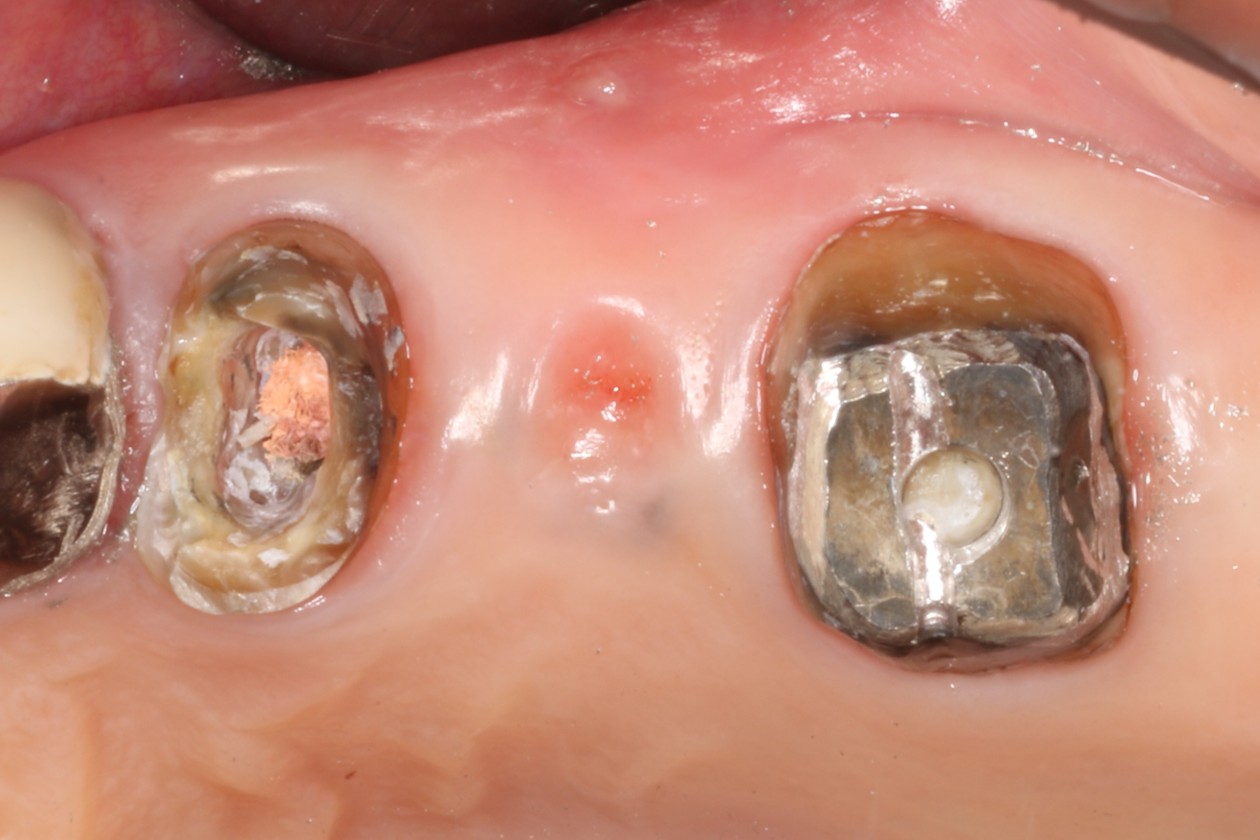

| 来院時の主訴 | 「左上の歯の周辺から膿が出て臭う。」 |

| 医院の診断 | 虫歯の再発、慢性根尖性歯周炎 |

| ココがこだわりのポイント☝ |

ラバーダム防湿とマイクロスコープを使用して丁寧に治療を行いました。 再根管治療のため、殺菌性があり歯を補強することのできる根管充填材料を使用しています。 |